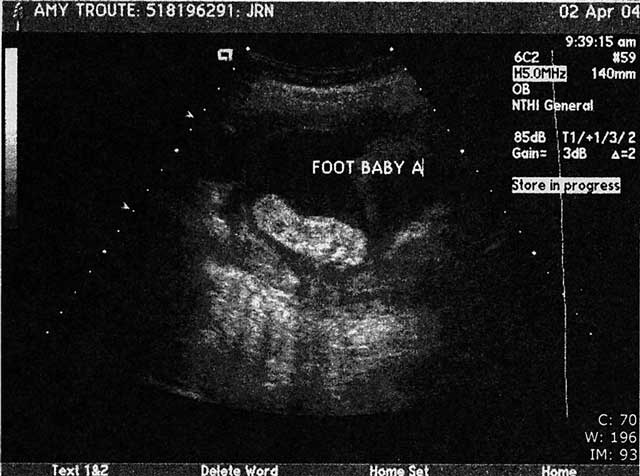

The babies are doing GREAT – measuring at 26 weeks, 1 day and I’m “technically” only 25 weeks 4 days along (hey – every little bit counts, right?).  Baby A is 2lbs 2oz and Baby B is an even 2lbs.  :o)  they’re kind of in “yin and yang” position now – so cool to finally get a visual on how they’re positioned.  Baby A is still the more active of the two – it’s feet are right up at my right rib cage, head down by my bladder and Baby B’s head is just above my belly button and feet are down at my left hip.  :o)  I can’t stop smiling, can you tell!!?